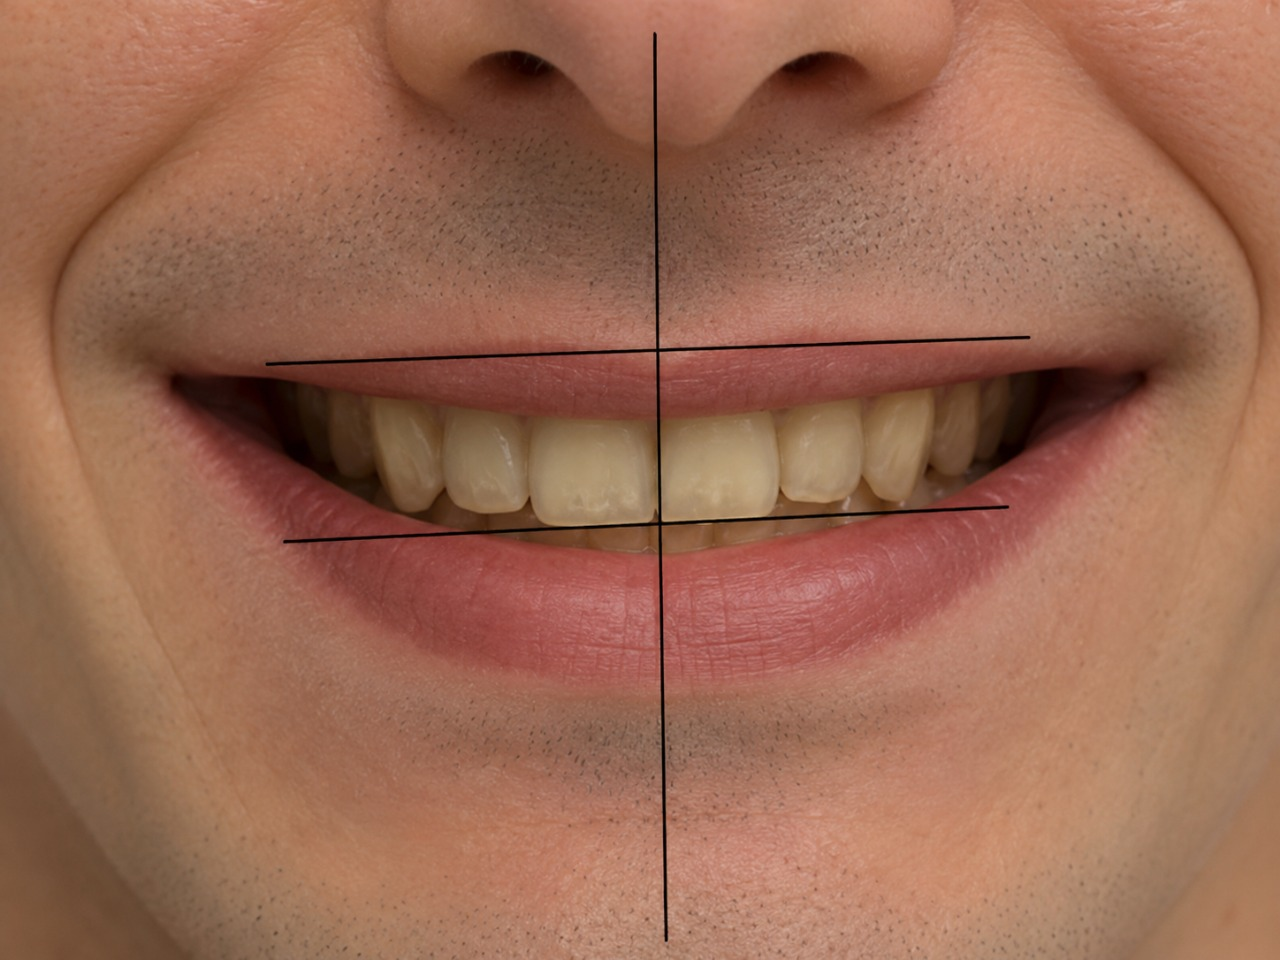

Привлекательная улыбка имеет свои вполне четкие стандарты:

- Линия верхних зубов (арка улыбки) должна быть параллельна нижней губе.

- Улыбка должна быть широкой. Чем больше зубов видно в момент улыбки, тем более привлекательной и открытой она воспринимается окружающими.

- Средняя линия улыбки должна совпадать с центром лица.

- Кроме того, чем заметнее при улыбке верхние зубы пациента, тем моложе он кажется. И, наоборот, демонстрация при улыбке нижних зубов добавляет годы.

Поэтому ортодонт обязательно учитывает все выше перечисленные параметры и планирует

такое передвижение зубов, чтобы, исходя из имеющихся возможностей, сделать улыбку

пациента максимально приближенной к идеалу. После грамотного ортодонтического лечения

пациент будет выглядеть более молодым и привлекательным без всякой пластической хирургии.

Результаты таких расчетов тоже отражаются в плане лечения.